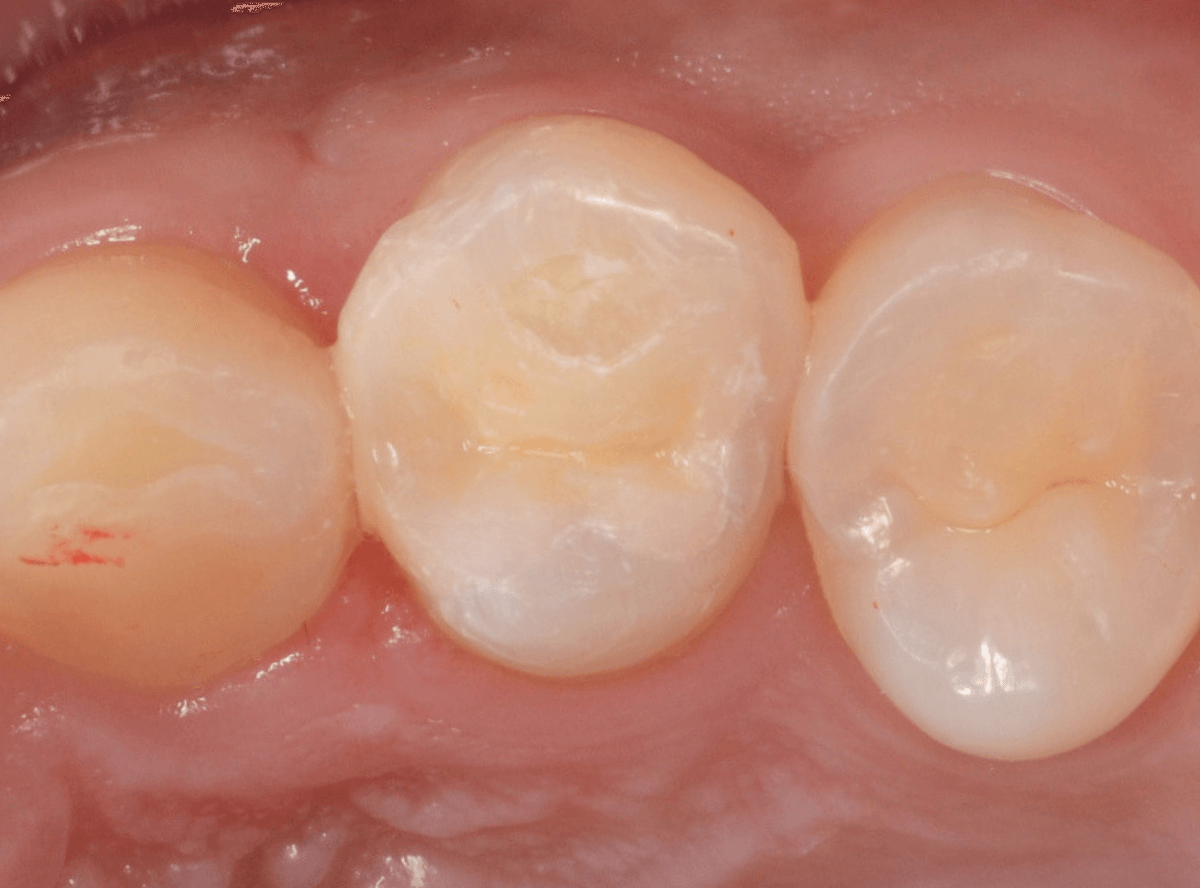

Case.21 奥歯のメタル・クラウンをジルコニアにやり替え

「上の奥歯の銀歯を白くやり替えたい」というご希望の患者さんです。

検査の結果、再製に問題なさそうでしたので、ジルコニア・クラウンで再製作する治療を進める事になりました。

メタル・クラウンを外すと、奥の歯の虫歯が見つかりました。

奥歯はおやしらずなので、抜歯も選択肢になるのですが、特にご希望されなかったため、一緒に虫歯の治療をすることになりました。

さし歯の土台の補修と、おやしらずの虫歯の処置をしたところです。

この状態で型をとります。

set後の写真です。

患者さんにも満足していただける仕上がりになりました。

治療前後の比較写真になります。